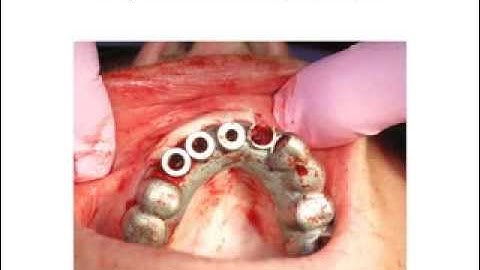

Pcube® - Stackable Guide System For Prosthetically Guided Immediate Loading